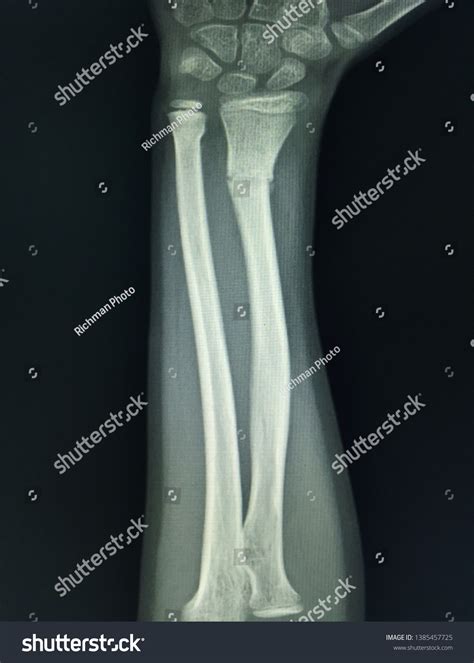

Position Purpose

Anteroposterior (AP) View The arm is flat on the table, palm facing up, providing a front-to-back view of the radius and ulna.

Lateral View The arm is turned 90 degrees, showing the side profile of the bones to check for displacement or angling.

Once the forearm X-ray images are captured, they are sent to a radiologist—a doctor who specializes in interpreting diagnostic images. They will look for:

• Fractures: Whether the bone is broken completely, partially (a hairline fracture), or fragmented (comminuted fracture).

• Alignment: Checking if the broken ends of the bone are touching or if they have shifted.

• Dislocations: Ensuring the bones of the elbow and wrist remain properly seated in their joints.